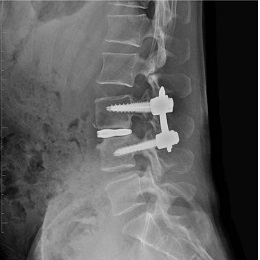

ME-PLIF/TLIF(内視鏡下腰椎椎体間固定術)

ME-PLIFは内視鏡とX線透視装置を使用した固定術と言われる手術です。全身麻酔後に、背部に18~20mm程の皮膚切開し、内視鏡の管を通します。変性した椎間板を取り除き、そこに腰骨から採取した骨を詰めたケージと言われる人工物を収め、脊椎を整形します。その後、上下に2箇所ずつ切開し、4本のスクリューと2本のロッドを挿入し、椎骨を固定します。主に腰椎すべり症など不安定性を伴う場合には、この手術が適応されます。